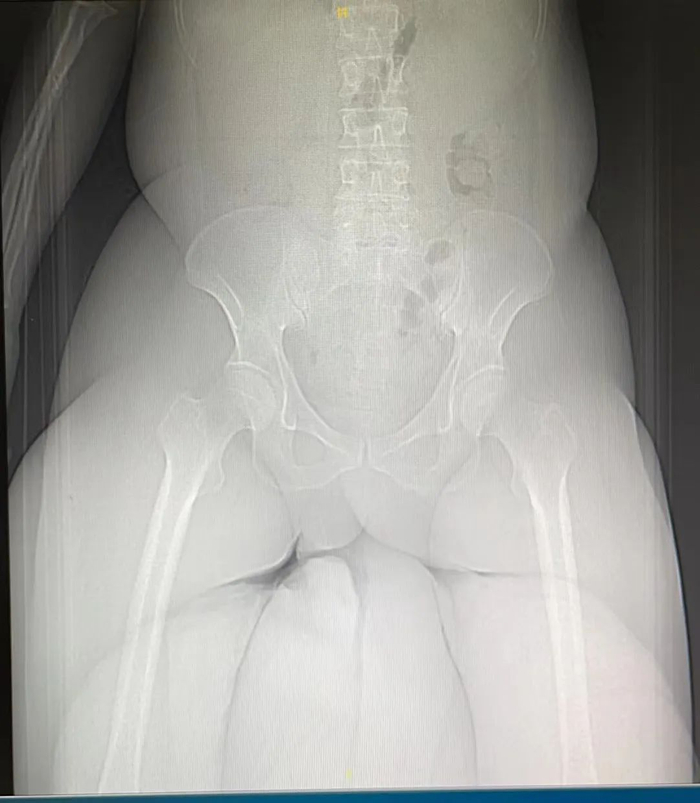

“核磁的线圈口不够大,人就堵在那里,根本躺不进去。我们只能退而求其次、改做CT。最后拍出来的影像仍不够完整。”姚海军说。

Z先生的阴茎阴囊象皮肿过于巨大,CT只能照射到部分肿块。(图源:受访者提供)